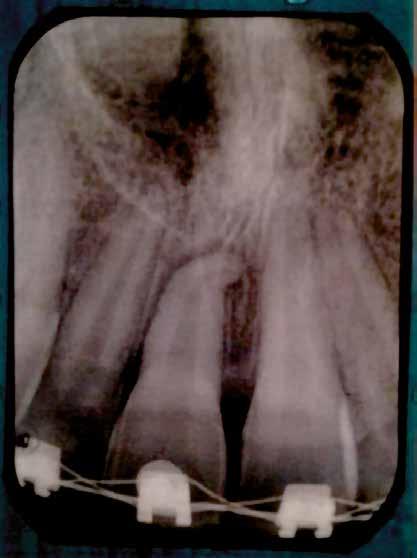

A 10 éves férfi páciens a felső frontfogai késői/nem megvalósuló előtörése miatt kereste fel a rendelőnket. A klinikai és a radiológiai vizsgálat során a jobb felső nagymetszőfog impakcióját észleltük (1. ábra). A fog horizontális tengelyállással és dilacerált gyökérrel rendelkezett. A felső dentális középvonal a fogak vándorlása miatt jelentős mértékben elcsúszott. A bal felső kismetszőfog is rendkívül kedvezőtlen pozícióba került.

Dr. Kazem Dalaie, dr. Samin Ghaffari, dr. Mazir Mir (Irán, Németország) 1. a ábra: Az intraorális felvételen jól látható a jobb felső nagymetszőfog lehetséges impakciójára utaló foghiány.

1. b ábra: A panoráma röntgenfelvételen megfigyelhető a teljes impakcióban lévő jobb felső nagymetszőfog. 1. c ábra: A CBCT felvétel is igazolja a jobb felső nagymetszőfog impakcióját.

sok korrigálása, valamint az impaktálódott fog előtöréséhez szükséges hely megteremtését követően, egy merev acél ív segítségével stabilizáltuk a fogakat. Ezt követően elvégeztük a jobb felső nagymetszőfog sebészi feltárását. A fog koronáját csupán lágyrész borította, ezért nem volt szükség a csontállomány elvételére. A felszabadítás során egy 975

nm-es hullámhosszon pulzáló üzemmódban alkalmazott lézert használtunk (LaserHF standard, Hager & Werken). A teljesítménye 3 W, az aktív ciklus-idő 50%-os, a vezetőszál átmérője pedig 0,4 mm volt (2. ábra). A lézert 150 másodpercen keresztül alkalmaztuk. A fogat borító lágyrészek eltávolítását követően egy láncos brekettet rögzítettünk a metszőfog bukkális felszínére. A műtétet követően nem tapasztaltunk vérzést, nem alakult ki oedema, valamint a páciens sem számolt be fájdalom vagy bármely egyéb kellemetlenség fennállásáról. A felszabadítást követően a páciens minden hónapban háromszor jelent meg a felszabadított területre ránövő lágyrészek és az íny lézeres eltávolítása céljából. A beavatkozások során ugyanazt a lézer készüléket használtuk, mint amivel a felszabadítást végeztük. Közvetlenül a felszabadítást követően megkezdtük a fog finom extrudálását a láncos breketthez kötött füzérgumi segítségével.

2. ábra: Az impaktált fog lézerrel asszisztált sebészi feltárása. 3. ábra: A kezelés megkezdését követő 15. hónapban megfigyelhető a sikeres felszabadítást, fogmozgatást és pozicionálást követően látható állapot.

A 975 nm-es hullámhosszt elsősorban sebészi beavatkozások végzése során alkalmazzák. Az ezzel a hullámhosszúsággal rendelkező lézersugarak csak kis mélységben képesek a lágyrészeket penetrálni, valamint hagyományosan nem ezeket szokták biostimuláció során használni. Ugyanakkor minden sebészi célra alkalmazott lézer körül megfigyelhetünk egy csökkenő intenzitással (azaz fényerővel) rendelkező gyűrűt, amely perifériáján biostimulációs hatások is létrejöhetnek. Az alacsony energiájú lézeres terápia (low-level laser therapy; LLLT) során a lézeres fejet a lágyszövetektől nagyobb

távolságban vezetve, az alábbi paraméterek mellett alkalmaztuk: pulzus üzemmód, 100 mW teljesítmény, 660 nm-es hullámhossz. A lézeres fejen lévő nyílás nagysága 0,125 mm2 volt (0,4 mm átmérő). A biostimuláció során egy megközelítőleg 7 cm2-es területet világítottunk meg a kérdéses fog vesztibuláris és palatinális oldalának megfelelően. A megvilágítás időtartama minden találkozó során 150 másodperc volt. A leadott energia 15 J, az energiasűrűség pedig 17J/ cm2 körül mozgott. A lézeres terápiát a kívánt fogpozíció eléréséig minden hónapban megismételtük. Ez a folyamat

4. a ábra: A CBCT felvétel igazolja, hogy a jobb felső nagymetszőfog megfelelő pozícióba került. Az ínyszél lefutása kedvező, a fog gyökere körül elfogadható mennyiségű csontállomány ábrázolódik, valamint a gyökérfelszívódás mértéke sem túl kifejezett.

6 hónapon keresztül tartott. Ennek megfelelően a fog körül található szövetek a felszabadítás, valamint a havi kontrollok során 975 nm-es (több mint 25 J/cm2 energiasűrűség) és 660 nm-es hullámhosszúságú (12–18 J/cm2 energiasűrűség) lézersugarakkal is megvilágításra kerültek. Az impaktálódott fogat megközelítőleg 7 hónap alatt tudtuk megfelelő pozícióba mozgatni (3. ábra). Az orthodoncia kezelés aktív szakasza 18 hónapon keresztül tartott. A fogívek végső nivellálását és a fogak végleges pozícióba rendezését 0.018 × 0.025-ös acélívekkel végeztük.

A kezelés befejezésekor a páciens mosolya drámai mértékben javult, továbbá a frontfogak elhelyezkedése és az ínyszél lefutása is szemmel látható módon kedvezőbbé vált (4. ábra). A kezelés végén készült CBCT felvétel nem mutatta

csontfelszívódás jelenlétét, és csupán minimális mértékű gyökérfelszívódás bekövetkezését igazolta.

4. b ábra: A panoráma röntgenfelvétel is alátámasztja a CBCT felvételen látottakat. 4. c ábra: Az intraorális felvételen megfelelő fogpozíciók és kedvező ínyszéli lefutás ábrázolódik.

A lézerrel asszisztált felszabadítás előtt készített felvétel.

periapikális felvétel.

felvétel.

5. a ábra: 5. b ábra: A végső állapotról készült 5. c ábra: A végső állapotról készült